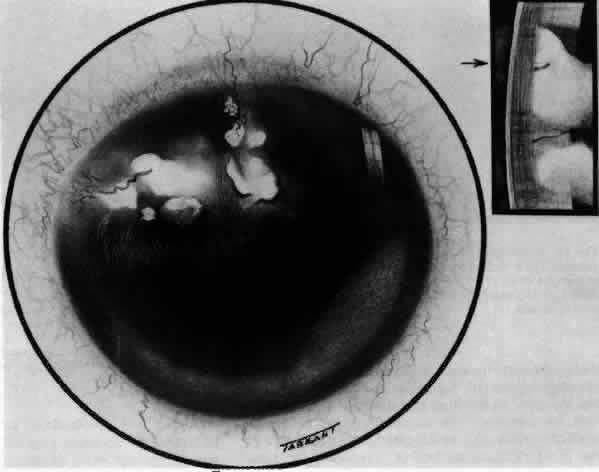

What is clinically represented solely by inflammation and edema is histopathologically

a granulomatous lesion of the sclera, the center of which

that would lead to granuloma formation. Remote from the granuloma, the

fibrocytes of the sclera become activated, the proteoglycan adjacent

to them becomes altered, and the collagen fibrils of the sclera

become unraveled (Figs. 23 and 24). These changes appear to take place prior to the invasion of the stroma

Fig. 23. Electron micrographs of scleral stroma at the periphery of an area of ulceration

in a patient with necrotizing scleritis. The left shows an active

fibroblastic cell, and the right shows collagen fibrils within intracellular

vacuoles (V) in the fibroblastic cell. (Left X15,375; right

X15,375) (Watson PG, Young RD: Changes at the periphery of a lesion necrotizing

scleritis: Anterior segment fluorescein angiography correlated with electron

microscopy. Br J Ophthalmol 68:781–789, 1984) Fig. 23. Electron micrographs of scleral stroma at the periphery of an area of ulceration

in a patient with necrotizing scleritis. The left shows an active

fibroblastic cell, and the right shows collagen fibrils within intracellular

vacuoles (V) in the fibroblastic cell. (Left X15,375; right

X15,375) (Watson PG, Young RD: Changes at the periphery of a lesion necrotizing

scleritis: Anterior segment fluorescein angiography correlated with electron

microscopy. Br J Ophthalmol 68:781–789, 1984)

|

Fig. 24. Electron micrograph of scleral stroma at the periphery of an ulcer in necrotizing

scleritis (same patient as in Figure 23) showing swelling and unraveling of collagen fibrils (arrows) in longitudinal

section (X29,270) and in transverse section (inset, X44,000). Fibrils

of all diameters are affected. (Watson PG, Young RD: Changes at the periphery of a lesion necrotizing

scleritis: Anterior segment fluorescein angiography correlated with electron

microscopy. Br J Ophthalmol 69:656–663, 1985) Fig. 24. Electron micrograph of scleral stroma at the periphery of an ulcer in necrotizing

scleritis (same patient as in Figure 23) showing swelling and unraveling of collagen fibrils (arrows) in longitudinal

section (X29,270) and in transverse section (inset, X44,000). Fibrils

of all diameters are affected. (Watson PG, Young RD: Changes at the periphery of a lesion necrotizing

scleritis: Anterior segment fluorescein angiography correlated with electron

microscopy. Br J Ophthalmol 69:656–663, 1985)

|